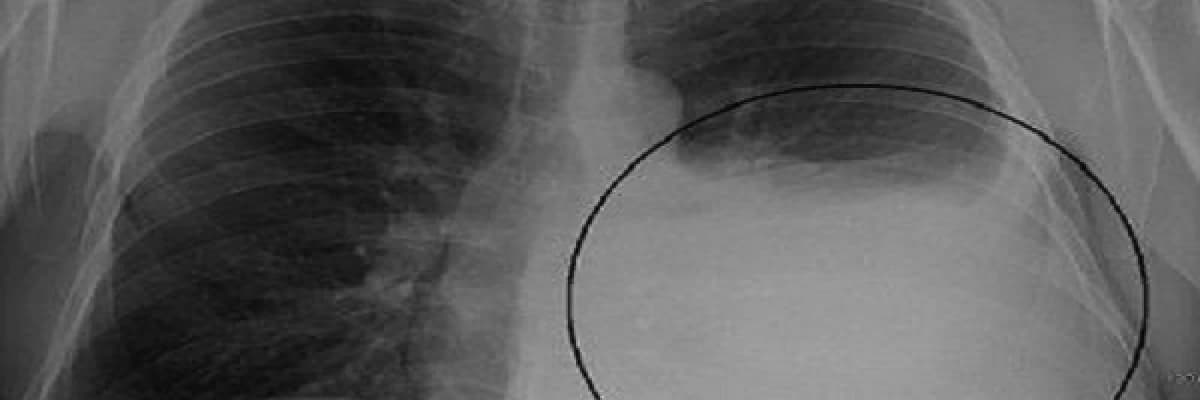

Plevra (akciğer zarı), akciğer ve göğüs boşluğunu örten 2 adet zardır. Akciğer dış yüzünü ve göğüs duvarı iç yüzünü saran bu zarlar arasında kalan boşlukta çeşitli içeriklerde su birikmesine plevral efüzyon denir.

Normalde, bu iki zar arasında çok az (20 ml) sıvı bulunur. Birçok akciğer veya akciğer dışı hastalığa bağlı olarak, ya sıvının salgılanmasının artması veya geri emiliminin azalmasına bağlı olarak bu zarlar arasında sıvı miktarı artar ve plevral efüzyon (plörezi) denilen tablo oluşur.

Akciğer grafileri ve Akciğer tomografisi ile plevral efüzyonlar görülür. Tanısı torasentez ile (kaburgalar arasından iğne ile sıvı alınması ) konulur. Torasentez ile tanı konulamazsa cerrahi yöntemler ile (kapalı plevra biyopsisi veya kapalı/açık akciğer ameliyatı) tanı konulur.